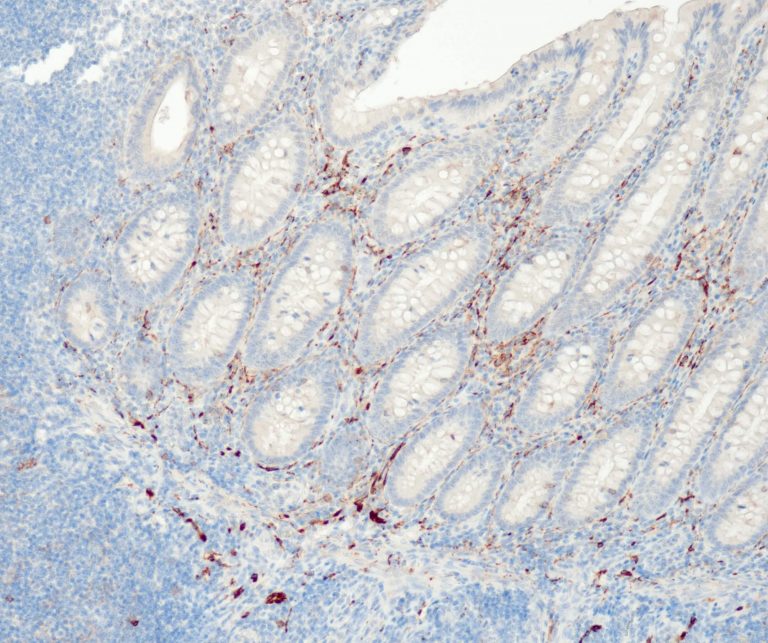

Gastrointestinal (GI) Pathology

General Marker

Infection Markers